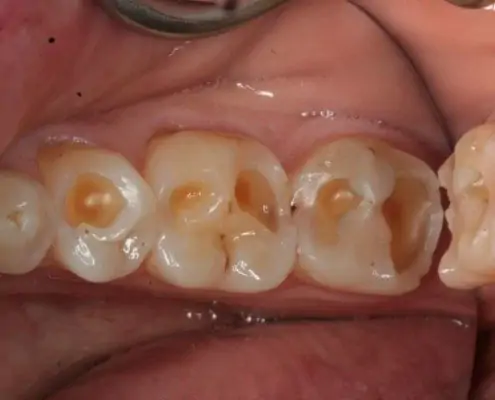

AvantAprès

Identifier les signes d’érosion dentaire

Les érosions dentaires peuvent être détectées lors d’un examen dentaire ou d’un détartrage. Des dents jaunies, une sensibilité accrue aux températures chaudes ou froides, ou des douleurs dentaires peuvent être des signes d’érosion dentaire.